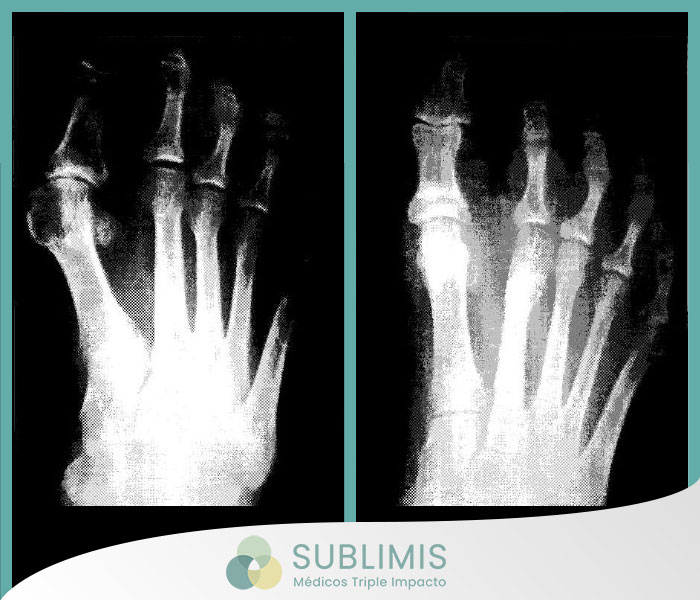

Hallux Valgus o Juanetes

El hallux valgus, que es el verdadero nombre científico, designa la popular y conocida deformidad del dedo gordo o juanetes. Se trata de una deformidad redondeada que aparece en la cara interior del pie producida porque el primer hueso metatarsiano cambia de eje, sale hacia delante y el dedo responde yéndose hacia fuera. Esto genera un desequilibrio que compromete al resto de los dedos y además puede producir callos y dolor.

Se trata de una técnica quirúrgica mínimamente invasiva útil para tratar las deformidades del antepié así como mantener el antepié biomecánicamente funcional.

En la cirugía percutánea la incisión es mínima (máximo medio centímetro) y a través de ella podemos introducir unas herramientas adecuadas, bisturís, fresas, etc., con las cuales y con la ayuda de un aparato especial de RX efectuamos toda las correcciones quirúrgicas que sean necesarias en los huesos deformados del pie.